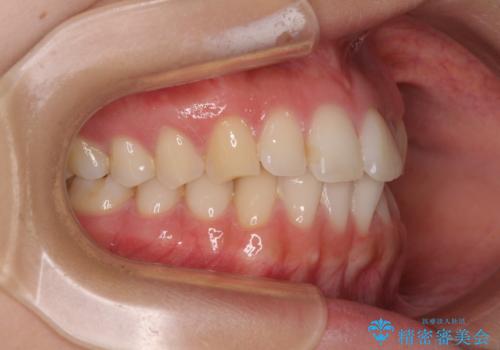

前歯の重なりをインビザライン・モデレートで矯正治療

- 上下前歯の重なりを気にして来院された患者様です。

安価なインビザラインパッケージを用いての治療を希望されており、デコボコの程度が中等度であったため、インビザライン・モデレートを用いて矯正治療を行うこととしました。